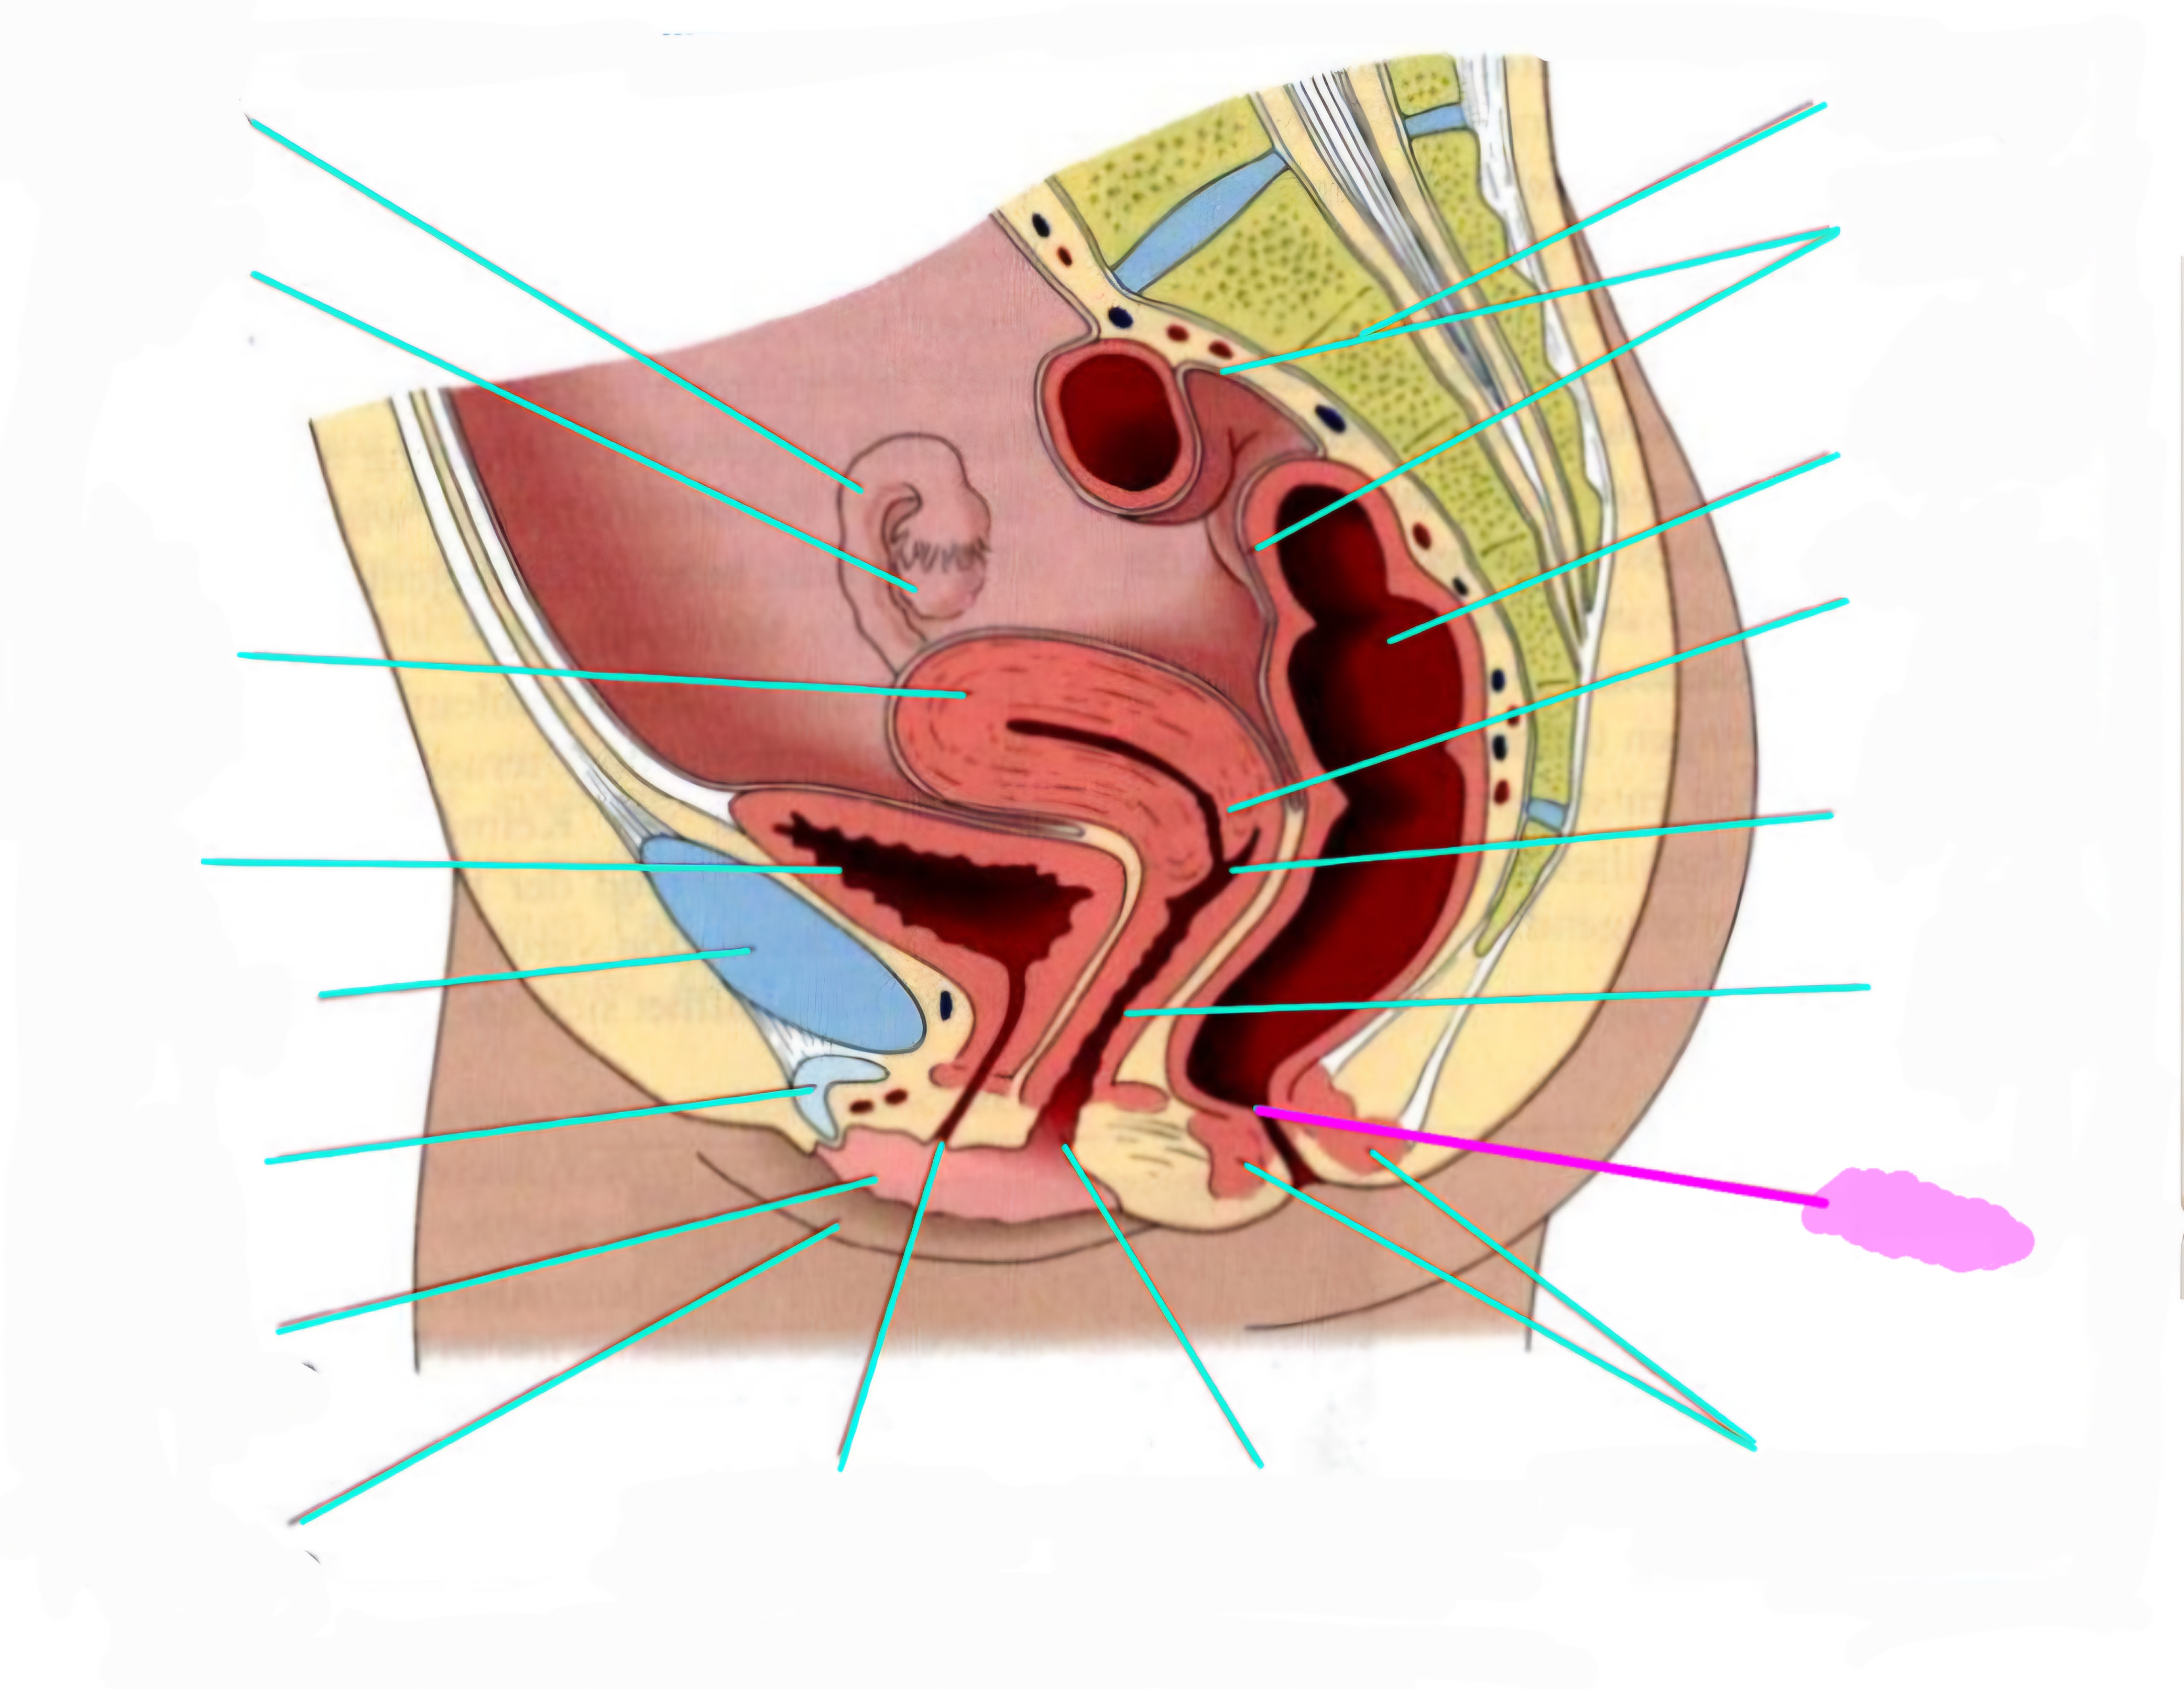

wbl. genital Anatomie

19 Terms

Tubea uterina (Eileiter)

Ovar (Eierstock)

Uterus (Gebärmutter)

Vesica Urinaria (Harnblase)

Symphyse

Klitoris

Labia minor pudendi (kleine schamlippen)

Labia Majoran pudendi (große Schamlippe)

Urethra (Harnröhre)

Introitus vaginae (Scheideneingang)

Sphincter ani externes (äußere Afterschließmuskel)

Anus (After)

Vagina (Scheide)

Portio (äußerer Muttermund)

Rektum (Mastdarm)

Zervix (Gebärmutterhals)

Peritoneum (Bauchfell)

Os sacrum (Kreuzbein)